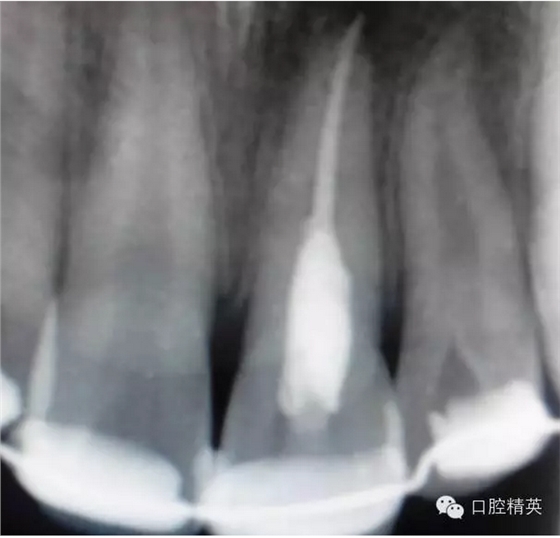

x線檢查:21牙槽窩空虛,窩內(nèi)未見(jiàn)其他遺留物。

圖3.患者21根尖片,牙槽窩空虛,無(wú)變形。

圖18.復(fù)位臨時(shí)固定后的x線根尖片?;颊哐栏c牙槽窩吻合。

圖23.樹(shù)脂+牙弓夾板固定完成后的x線片影像

圖5.拆除樹(shù)脂夾板前的x線根尖片影像,21根尖出現(xiàn)少許吸收。大家擔(dān)心的情況出現(xiàn)了。